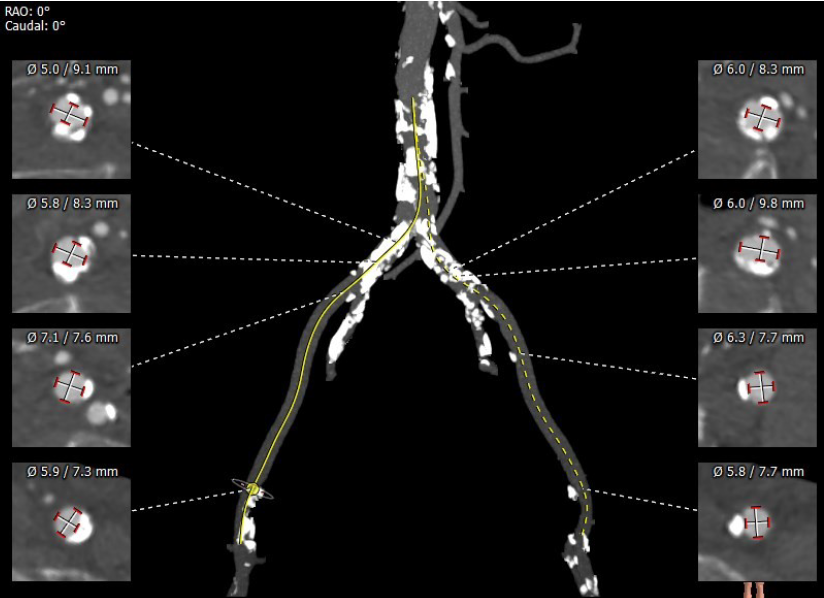

超声心动图显示,主动脉最大流速482cm/s,最大压差93mmHg,平均压差50mmHg,LVEF65%。CT显示主动脉瓣为TYPE2型二叶瓣,严重钙化,右无、左无可见粘连伴钙化,瓣环平面可见钙化,钙化延伸至流出道及二尖瓣前叶根部,左冠高度约12mm,瓣叶长度14.9mm,存在一定左冠风险,法式窦平均直径33.7mm,STJ高度约21.8mm、直径约30.2mm。

主动脉弓部走行较平缓,弓顶部可见少许钙化,主动脉弓部三根毛开口未见明显狭窄征象、未见发育变异,胸主动脉、腹主动脉走行较平直、腹主动脉多发严重钙化斑块,管腔未见明显狭窄,双侧髂动脉-股动脉走形迂曲,双侧髂动脉多发严重钙化斑块,部分呈半环形、马蹄形分布,右侧股动脉可尝试做为主入路,左股动脉作为脑保护入路。虚拟瓣环直径25mm,左室流出道平均直径23.3mm,拟植入VenusA Plus 23/26号的瓣膜。术中balloon sizing确认瓣膜型号,同时确认冠脉风险。